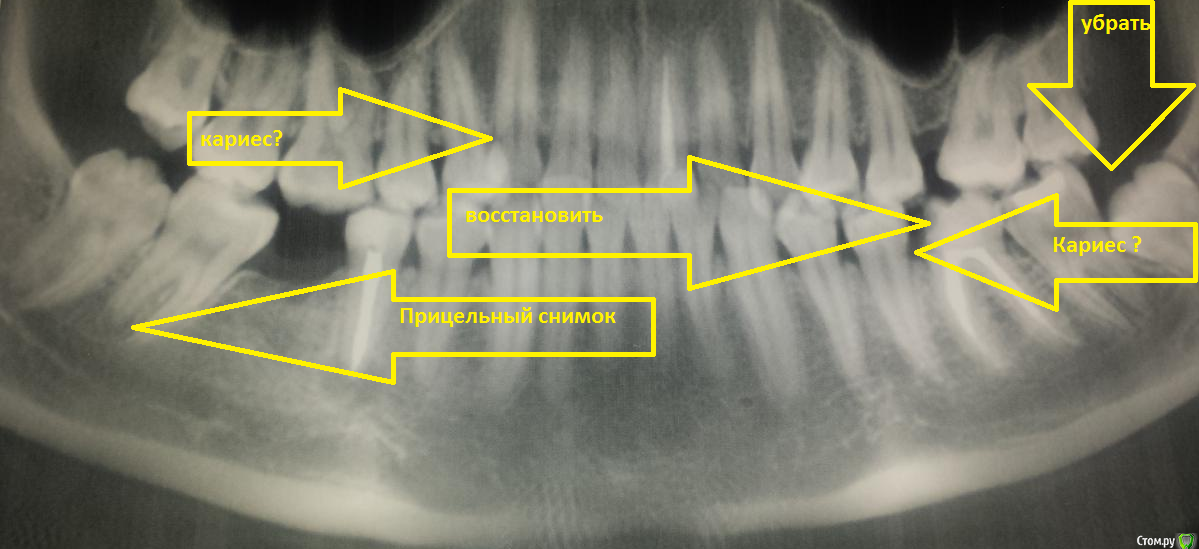

EkaterinaVVL Опубликовано 23 июня, 2016 Поделиться Опубликовано 23 июня, 2016 Здравствуйте, помогите пожалуйста возможно ли сохранить зуб? После проведения ОПТГ обнаружили кисту зуба (5-ка снизу) была в нескольких клиниках, мнения врачей расходятся одни говорят удалять, другие лечить. Посмотрите пожалуйста и подскажите что делать в такой ситуации? Целесообразно удаление? У меня 6-ки нету вот и переживаю как дальше, если все таки удалять... но и с очагом инфекции ходить опасно тк планируется беременность. Один врач заметил кисту на 6-ке снизу слева, есть ли там киста?(понимаю что скорее всего нужно делать прицельный снимок зуба). После лечения(удаления) планирую ставить брекет-систему. Фото ОПТГ+ прицельный снимок(5-ки, фото правда не очень) прилагается.Очень нужна помощь, заранее большое спасибо Ссылка на комментарий

___49___ Опубликовано 24 июня, 2016 Поделиться Опубликовано 24 июня, 2016 (изменено) Вариантов для сохранения 2 .- перелечить канал у грамотного эндодонтиста ..- произвести резекцию корня у грамотного хирурга стоматолога ( так как рядом выход нервно-сосудистого пучка ).Первый вариант предпочтительнее , но при возникновении затруднений( непроходимый канал и т.п.) возможен и вариант 2 . Оба варианта потребуют рентген контроля, в вашем случае если после пройденного лечения в скором времени вы забеременеете , врачу придется ориентироваться только на клинические проявления (при отрицательной динамике будет показано удаление зуба), при положительной динамике после родов , вам проведут рентген контроль после которого можно будет сказать происходит восстановление костной ткани или нет - шанс не 100% но все равно достаточно хороший на сохранение зуба ( исходя из предоставленной вами информации т.к. возможны нюансы ....форум - это не очный прием ). Изменено 24 июня, 2016 пользователем ___49___ Ссылка на комментарий

Bier Опубликовано 25 июня, 2016 Поделиться Опубликовано 25 июня, 2016 Канал вроде хорошо пролечен. Надо залезть в зуб еще раз, если там не пропустили доп. канал, то можно подумать о резекции (только грамотные нужны специалисты, чтобы по "старинке" не сделали) с ретроградной пломбировкой. 2 Ссылка на комментарий

vse32 Опубликовано 28 июня, 2016 Поделиться Опубликовано 28 июня, 2016 Надо залезть в зуб еще раз, если там не пропустили доп. канал, то можно подумать о резекции Периодически вижу снимки на которых красивая пломбировка и киста. Практически всегда там гутта. Подозреваю недостаточную медобработку. Качественный ретрит - вероятнее всего решит проблему. Ссылка на комментарий